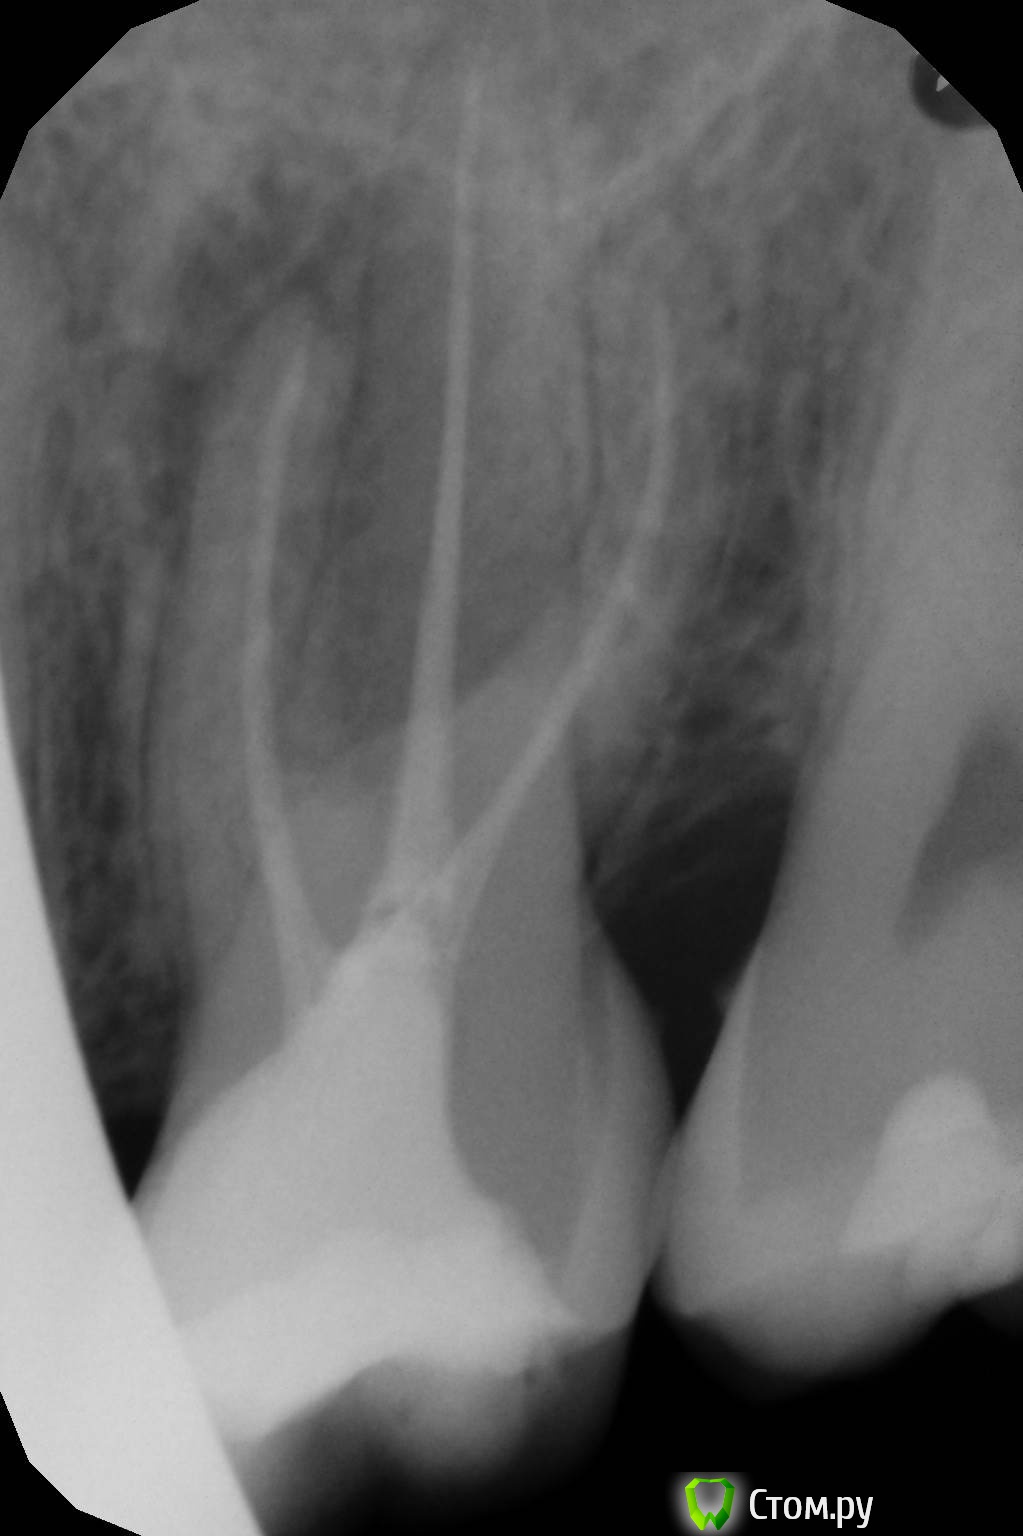

oksanab Опубликовано 9 октября, 2014 Поделиться Опубликовано 9 октября, 2014 (изменено) мне лечили 26-й зуб и медсестра озвучила, что нет 40-го и 38-го штифта .В итоге врач поставил просто эндометазон без гуттаперчей. Это я узнала, когда мне зуб вскрыли и стали перепломбировывать один канал, ввиду того, что паста там была не застывшая, мягкая. Является ли это ошибкой терапевта, когда паста мягкая в канале? . Плохо ли, когда эндометазон без гуттаперчи(судя по всему не было 40-го )? И почему ,как вы думаете, уже другой терапевт перелечила только центральный канал и не тронула остальные, хотя я просила об этом(потому что ортопед попросил). Она только загерметизировала остальные два канала(возможно апексом, не знаю, а вот центральный канал апексом верхушку корня залила). Достаточно ли этого, или лучше все-таки перепломбировать и два остальных канала?(в одном из них судя по всему перфорация, на другом - лекарство выведено за канал ,а может эндометазон за канал с лечебной целью выведен.... В выписке предыдущий врач не отметил, какое конкретно лекарство за каналом было выведено. Прилагаю снимки, на первом три канала 12 лет назад, на втором и третьем - перелечивание и пломбировка эндометазоном всех трех каналов(просто два снимка в разных клиниках ,но суть одна), да еще и скол зуба появился небольшой(ортопеды говорят, поправимо), и на третьем снимке перепломбировали только центральный канал. Нормально ли перепломбировали хоть средний канал? на мой взгляд как-то верхушка его странно расширилась, была поуже на 2-м и 3-м снимке(пломбировали методом латеральной конденсации). Подскажите пожалуйста, что думаете? Изменено 9 октября, 2014 пользователем oksanab Ссылка на комментарий

oksanab Опубликовано 10 октября, 2014 Автор Поделиться Опубликовано 10 октября, 2014 (изменено) да, но как перепломбировали средний канал? подскажите пожалуйста. Мне сделали около 6 снимков, тут не все даже, но врач утверждает, что нет никакого 4-го канала. Изменено 10 октября, 2014 пользователем oksanab Ссылка на комментарий

Паращук Роман Опубликовано 10 октября, 2014 Поделиться Опубликовано 10 октября, 2014 (изменено) Сравните снимки.Ты видишь суслика? Нет? И я нет,а он есть! (с)ПиСи Пропущенный канал,перфорация,мат-ял за верхушкой. Зуб уже визу в плевательницу открыл.http://s020.radikal.ru/i708/1410/b7/ad9c402a2f4c.jpghttp://s43.radikal.ru/i099/1410/5f/23581663b182.jpg Изменено 10 октября, 2014 пользователем Паращук Роман Ссылка на комментарий